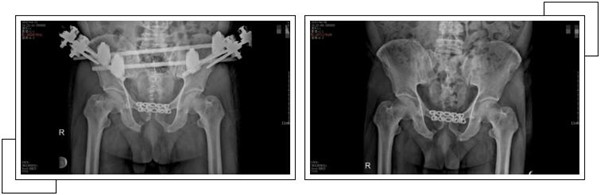

二周后,趙大叔病情穩(wěn)定,身體各方面條件符合手術(shù)指征后,骨科中心副主任羅軍帶領(lǐng)手術(shù)團(tuán)隊(duì)為其進(jìn)行了骨盆骨折、恥骨聯(lián)合分離、雙側(cè)髂骨骨折、右側(cè)恥骨上下支骨折切開復(fù)位內(nèi)外固定術(shù),手術(shù)一個(gè)半小時(shí)順利完成。